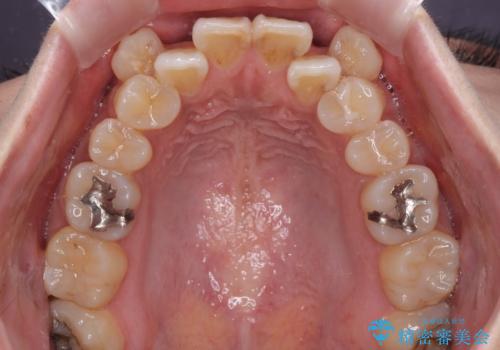

目立たない装置を希望されたので、上顎が裏側装置のハーフリンガルを選択し、上下左右の小臼歯(計4歯)を抜歯して矯正治療を行うこととしました。

- 治療費の目安: 130万円(税込)費用は治療当時の料金となります